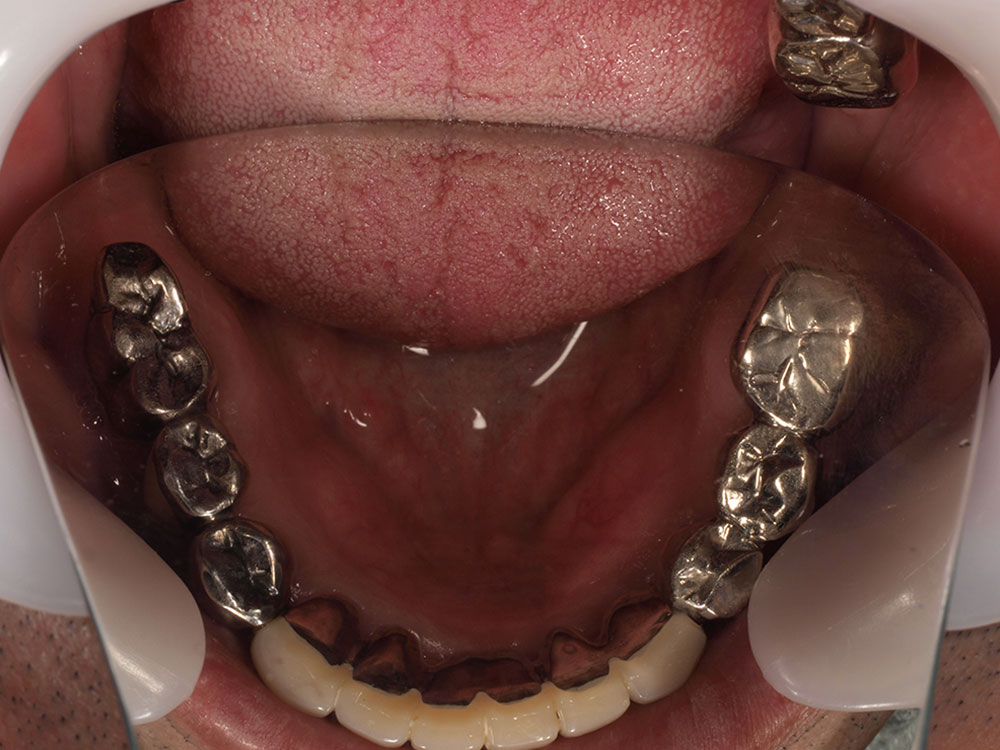

- 主訴

- 入れ歯が気持ち悪く、しっかりと食べれない。本当につらい。美味しく食べて、豊かな人生を過ごしたい。

- 処置内容

- 上顎6本(オールオン6)

- 治療費用

- 上顎350万円(税込)

- 治療期間

- 上顎1年(仮歯まで8か月)/約10回

- リスク

- 上部構造物、仮歯の破折、術後の腫れ(3日)、人工歯根脱落のリスクがあります